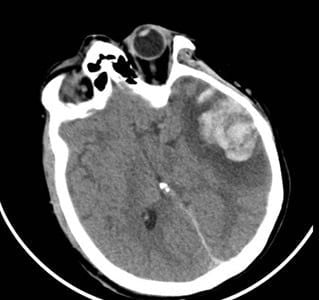

Cùng lúc đó, mẹ của anh là người bệnh G.N. (nữ, 53 tuổi) cũng nhập viện trong tình trạng lơ mơ, dập não thái dương lượng lớn. Sau khi cân nhắc kỹ lưỡng, các bác sĩ đã quyết định điều trị bảo tồn thay vì phẫu thuật để hạn chế tổn thương thứ phát. Quyết định này đã mang lại hiệu quả rõ rệt, người bệnh dần tỉnh táo và cải thiện chức năng ngôn ngữ. Sau 10 ngày điều trị tại Khoa Ngoại Thần kinh, bà G.N. đã hồi phục và được xuất viện.

Hình 2: Phim CT scan ngày 06/01/2026 người bệnh G.N. cho thấy vùng dập não xuất huyết thái dương lớn kèm phù tổ chức xung quanh.